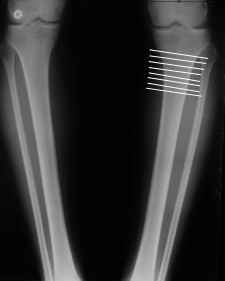

Судя по снимку у девушки имеется внутренняя установка надколенников...

Как у нее с торсионным статусом? Бедро? Голень? КТ? Торсиометры? А то, куда будут

смотреть надколенники после вашей коррекции - тоже существенный

косметический момент. Или не так?

Клинически глядел - вроде нету большой торсии.

AVM> Судя по снимку у девушки имеется внутренняя установка надколенников...

AVM> Как у нее с торсионным статусом? Бедро? Голень? КТ? Торсиометры?

Похоже, немного есть. Думаю пренебречь.